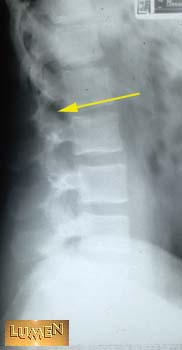

What passes through here?

Spinal nerve.